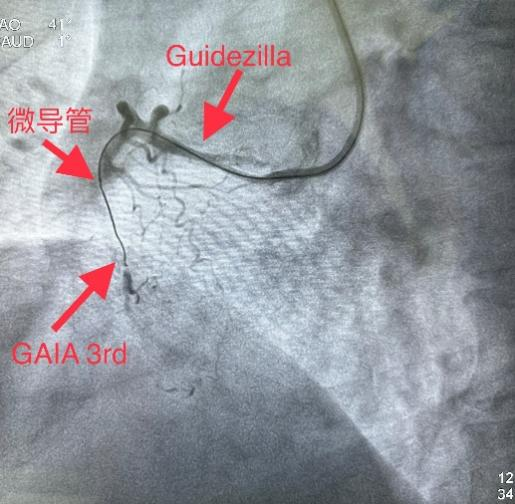

3月8日经过充分的术前准备,雷新军教授带领景林德博士和蔡安琪医生按照预定方案为患者实施了手术。冠脉造影示:RCA 2段慢性闭塞合并重度钙化,闭塞段长约30 mm,同向桥侧支供血使其远段显影(图3a);前降支散在斑块伴钙化,狭窄约25%-50%,并通过间隔支侧支循环向右冠逆向供血(图3b);回旋支11段狭窄约75%(图3c)。决定干预右冠:指引导管到位后在Guidezilla的支撑下,经Corsair微导管仔细操控GAIA 3rd穿过闭塞段进入远端血管真腔(图3d,e);然后通过微导管交换成旋磨导丝,使用1.5 mm Burr进行冠脉内斑块旋磨并抛光(图3f),造影见右冠恢复TIMI 3级前向血流,但2段残余狭窄最重处仍达90%(图3g);遂经导丝送入3.0*12 mm“Shockwave”冲击波球囊分段进行血管内碎石术:首先将压力充盈至4 atm后开始释放脉冲,松解钙化斑块,然后再将充盈压升至6 atm维持10秒,对靶病变进行低压球囊扩张成形(图3h);再次造影见右冠2段局限性夹层,闭塞段残余狭窄<10%(图3i),效果非常满意,遂由远及近衔接植入BioFreedom支架(图3j),历时约1小时手术成功,病人安返病房。

图3 经皮冠脉介入治疗